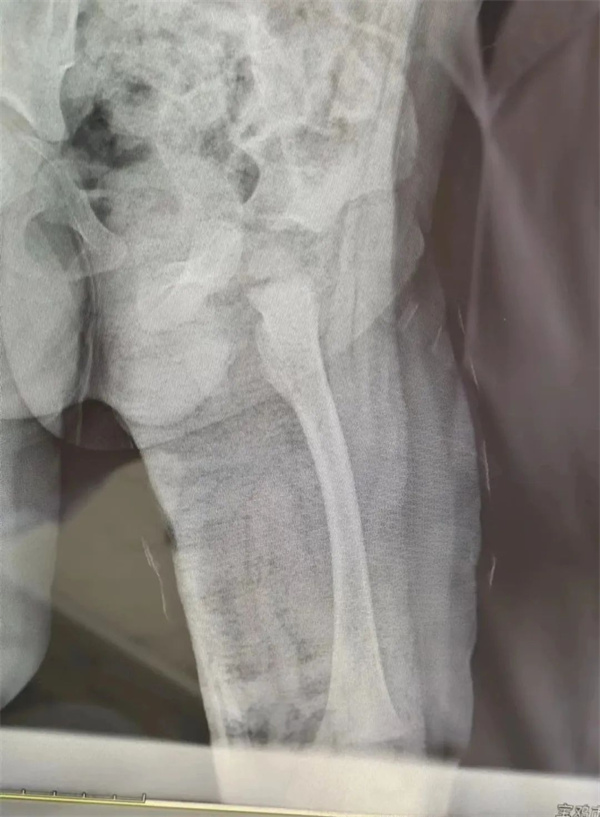

手术复位、石膏固定

王文亮组织科室医生进行讨论研究后建议:如果选择手术治疗,有损伤骨骺可能,影响患儿骨骼发育,而且二期需要取除内固定装置,会给患儿造成较大的身体和心理创伤,家长不愿接受;而选择手法复位治疗的话,凭借小儿自身强大塑型能力,可以达到相当好的治疗效果。但压力就给到医生这边,因为复位后随时都有再次移位的可能。经王文亮与孩子父母亲反复沟通后分析利弊后,决定为患儿进行手法复位。在麻醉手术科全力配合下骨一科团队急诊为患儿实施全麻下“左股骨粗隆下骨折闭合手法复位+髋人字石膏固定术”,术中透视见复位满意。

术后第三天